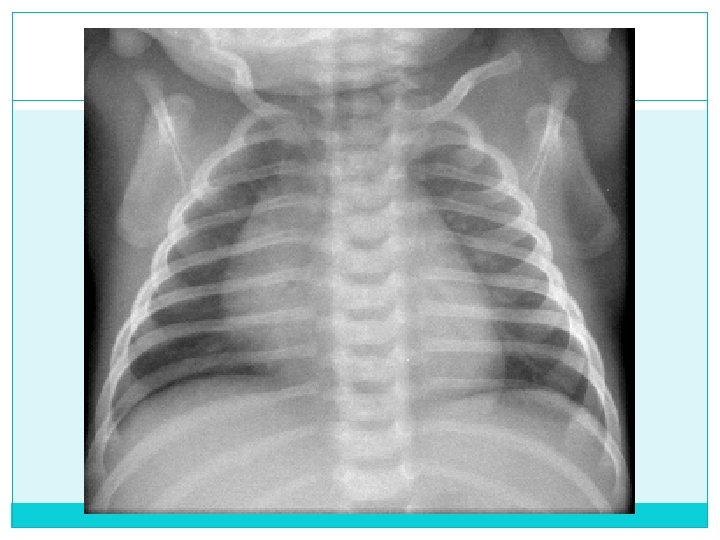

Espirada

Bien Inspirada Vs Espirada